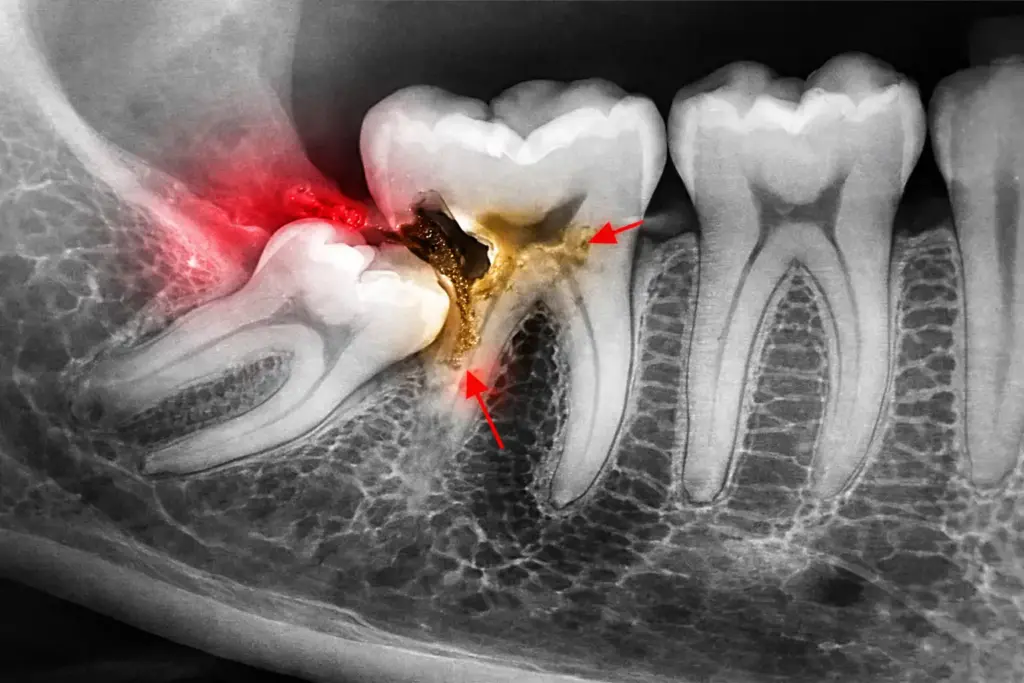

Impacted teeth are teeth that do not emerge fully into the mouth due to lack of space, improper position, or obstruction by other teeth or bone. Wisdom teeth are the most commonly impacted, but other teeth can also be affected. If left untreated, impacted teeth can lead to pain, infection, and damage to nearby teeth.

Damage to adjacent teeth seen on X-rays

Clinical examination and X-rays

Assessment of tooth position